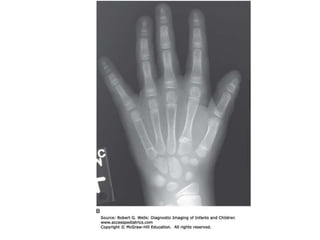

characteristic pronounced

hypoplasia of the lateral

proximal tibial epiphysis

with marked genu valgus.

The carpal bones have delayed maturation but the

maturation of the phalanges is accelerated.